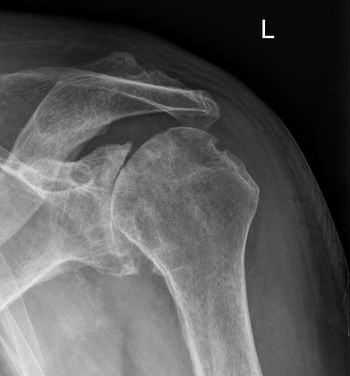

Em um ombro artrítico O revestimento da cartilagem é mais fino do que o normal ou completamente ausente. O grau de dano e inflamação da cartilagem varia com o tipo e estágio da artrite A cápsula do ombro artrítico está inchada O espaço articular é estreito e de contorno irregular; isso pode ser visto em uma imagem de raios-X. Esporões ósseos ou osso excessivo também podem se acumular ao redor das bordas da articulação

Os médicos diagnosticam a artrite com um histórico médico, exame físico e raios-X da parte afetada. A tomografia computadorizada (TC) e a ressonância magnética (MRI) também são realizadas para diagnosticar a artrite.